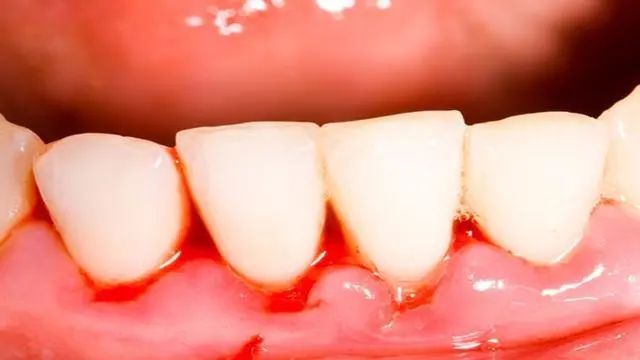

1、牙龈红肿出血:牙周炎主要表现为牙龈红肿、出血,不仅在刷牙时出血,有时在说话或者咬硬物时也会出血,有时可自发出血。

牙龈颜色暗红,由于水肿显得比较光亮。健康的牙龈,即使用力刷牙或轻探龈沟均不引起出血。而在初期和早期龈炎阶段,轻探龈沟即可出血。它比牙龈颜色的改变出现得早些,而且也较客观。故探诊出血,可作为诊断牙龈有无炎症的重要手段。